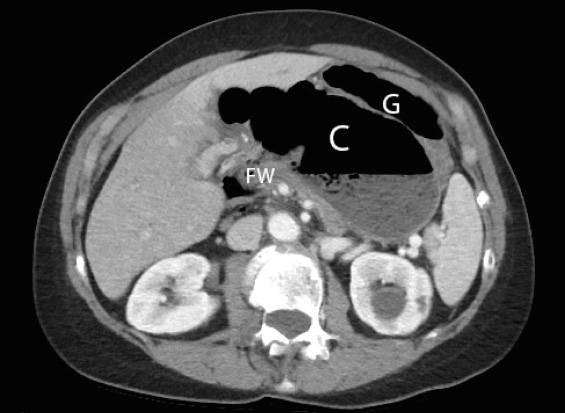

Figure 1. A computerized tomography in axial orientation shows the distended cecal loop (C) containing an air fluid level, situated inside the lesser sac behind the relatively decompressed gastric bubble (G). The foramen of Winslow is also visualized (FW) with colonic gas spanning either side.

Her body mass index was 21.5 kg/m2. Physical examination demonstrated a very distended abdomen with mild tenderness at the epigastrium without rebound and guarding. Laboratory values were unremarkable, with normal white blood count (Table I). A computerized tomography (CT) scan of the abdomen and pelvis with intravenous contrast demonstrated apparent cecal displacement, with volvulus into the lesser sac without any bowel compromise or signs of ischemia (Figure 1).

Abdominal plain films can demonstrate a “coffee bean” sign with concomitant pneumoperitoneum or pneumatosis consistent with complications such bowel perforation and ischemia [13]. However, plain film is unable to confirm diagnosis in up to 85% of cases [1]. CT scan is the diagnostic imaging of choice, given its high sensitivity (96%) and specificity (93%) for large bowel obstruction, and is also able to identify important anatomy and concurrent incidental findings [14]. In this scenario, the decompressed stomach and the large retrogastric airspace containing a colonic conformation were telling signs that the colon had entered into and became obstructed in the lesser sac.